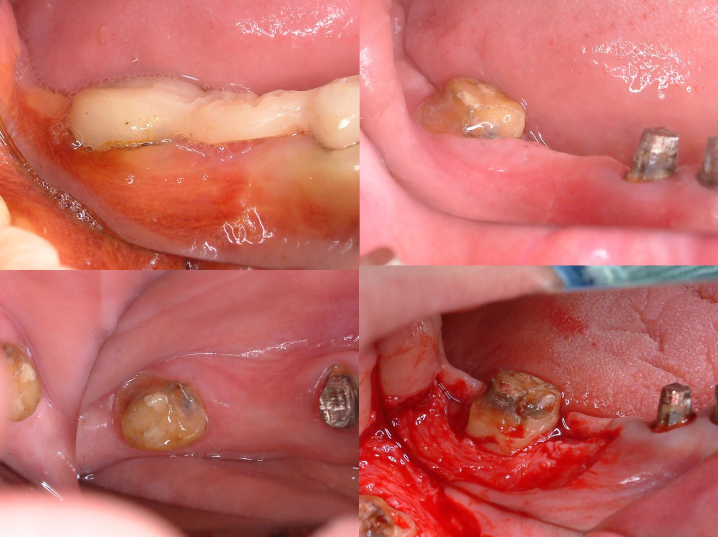

歯肉形成外科の術中所見です。最終的は被せもののイメージを行いながら歯茎と顎の骨の整形を行いました。

術前と術後の比較写真です。

歯茎の下の方まで虫歯でしたが歯茎の上までしっかりと健康な歯の部分を出すことができました。

ほぼ骨内には埋入できましたが、骨の厚みが足りないため、人工骨を移植し縫合しました。

インプラントの周囲に固い歯茎(角化歯肉)があるとしっかりと歯ブラシがあてることができます。

インプラントの周囲に固い歯茎を作るために歯茎(角化歯肉)の移植を行いました。